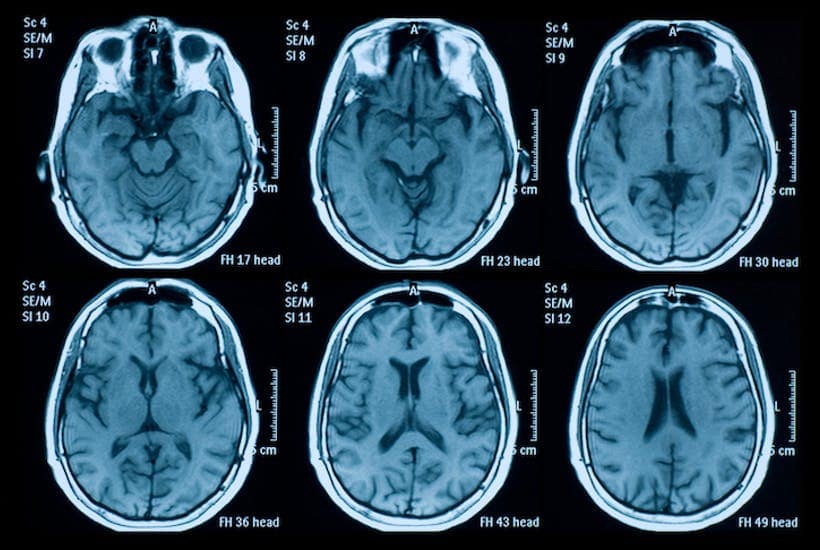

magnetic resonance images of brains in mri scans - stock photo

The wonders of modern medicine, hey? I have been stressed out for most of the week, because I was scheduled to have an MRI scan of my brain this afternoon. The reason that I needed to get this done is because my prolactin is very high, and although a medication that I take elevates prolactin, my doctor wanted to rule out a tumour on my pituitary gland that can also cause elevated prolactin.

In order to take an MRI scan of my pituitary gland, I needed to be injected with a contrast solution. When my doctor told me what the procedure would be, I was even more dubious about getting this scan done.

For a contrast MRI, first they insert a drip into your vein, and then you go into the MRI machine for about 15 minutes, while it does all sorts of different scans.

I sat there with the drip in for about fifteen minutes and waited for the MRI machine to be free. Then they finally took me in. I was terrified. My doctor told me that people can get quite anxious and claustrophobic inside the machine. However it was not too bad.

They locked this kind of cage over my head, gave me earplugs, put padding around my head, gave me an alarm in my hand to press if I needed to come out for some reason (which was comforting), and wheeled me in.

It was actually not that stressful, and they played music – Florence and the Machine, so it was quite relaxing really. Also, there was a mirror in the top of the head cage, so that I could see the radiographer taking images, and he would talk to me through a microphone, periodically. So that I knew what was happening.

Magnetic resonance imaging scanner does not use any radiation x-rays. To get pictures of your brain, the MRI scanner uses very strong magnet. It gives reliable scanning results of the brain and the spinal cord which is totally a safe procedure. However, it is an expensive procedure but these days’ medical experts are relying more on MRI scans.